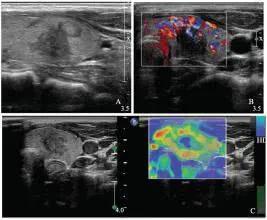

1、甲状腺结节钙化 由于大约80%左右的恶性肿瘤内有钙化,而只有大约50%的良性结节内才有钙化,因此钙化是一个甲状腺癌的重要标识。 当然,并非所有类型的钙化都提示甲状腺癌,这其中还可以细分为:

1)微钙化:表现为后方带或不带声影的点状强回声,大多为沙粒体或髓样癌内部淀粉沉积物继发的钙化和纤维化,在大约40%~60%的甲状腺癌内可有此表现;

2)边缘钙化:指的是位于甲状腺结节边缘部位的钙化,常见于结节性甲状腺肿,是良性结节的标志;

3)粗钙化和钙化斑:是指单个粗大钙化灶,且在钙化区域超声未显示甲状腺结节,常见于甲状腺良性病变,比如结节性甲状腺肿、甲亢等甲状腺弥漫性病变中。许多老年人的甲状腺内粗钙化、边缘钙化或钙化斑,大多是由于甲状腺组织退变、炎症以及营养不良造成的。

2、结节边界不清晰 大约80%~90%的甲状腺恶性肿瘤的边界是不清或者欠清晰的,而大部分良性结节的边界都是非常清晰的,仅有15%左右边界不清的表现。

3、回声不均匀 研究发现,>90%的恶性肿瘤的回声不均匀。虽然也有2/3的良性结节的回声不均,但一旦B超发现的结节回声均匀,基本上可以认为其恶性可能很小了。

4、囊性成分不均匀 一般来说,囊性成分越多,良性结节的可能性越大。那些含纤维分隔的多房性囊性、呈“蜂窝状”图像的结节基本就可以肯定是良性结节了。而小的囊性结节内有强回声伴后方增强,即伴“彗星尾征”伪像的囊性结节也是良性结节的特征性表现。而囊实性成分混合的结节,尤其是囊壁有结节状隆起,囊壁厚度不均匀者都要高度怀疑恶性肿瘤的可能性了。

5、低回声结节 几乎所有的恶性结节和大部分(约90%)的良性结节都是属于低回声结节,一旦发现结节内回声属于等回声或高回声的,基本可以看作良性结节处理了。

6、结节内血流表现 各种良恶性结节内均会有血流表现,但恶性结节还是有其特异性的。一般恶性结节内的血流在彩色多普勒超声上显示为多血供型,而且结节内血流紊乱。结节性甲状腺肿的特点是可见血流在结节间穿行、绕行;而腺瘤的内部血流信号呈点状或条束状分布;当发现腺瘤周边血流信号较丰富时,一般提示是囊腺瘤。